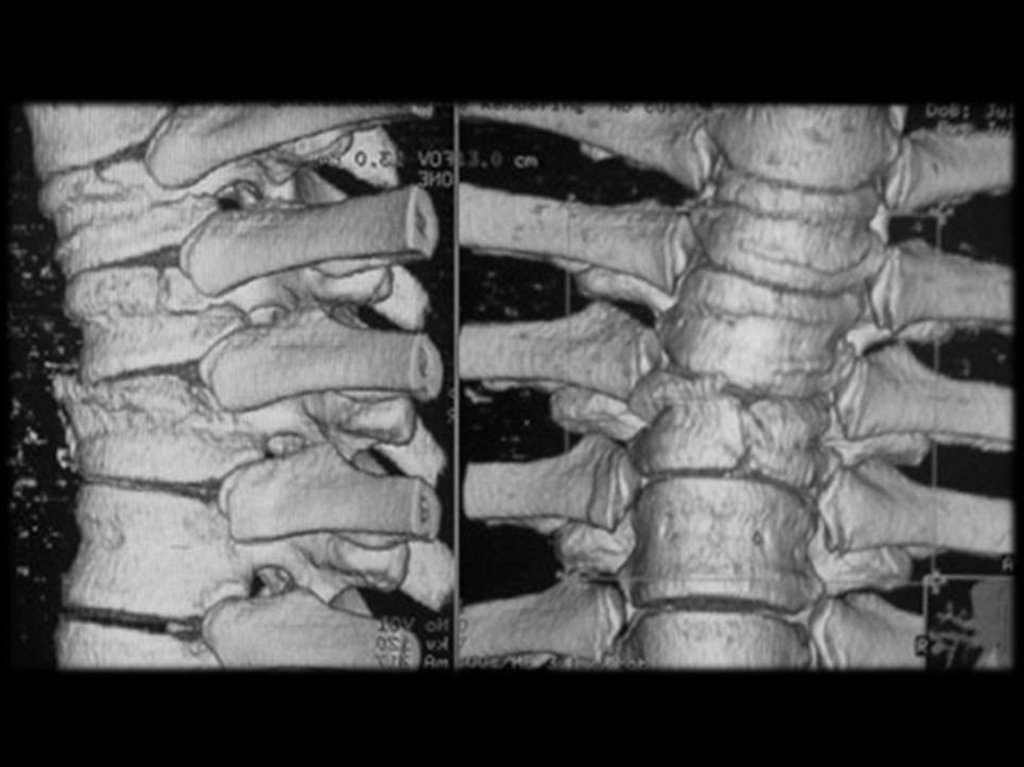

R-признаки при ОП (R-графия позвонков в

боковой проекции), потеря костной массы

при этом составляет 20 – 30%.

разряжение губчатой кости;

уменьшение количества трабекул на

единицу плотности кости;

повышенная прозрачность тел позвонков;

видны вертикальные трабекулы;

“рамочная” структура

тел

позвонков

(истончение и резкая подчёркнутость

контуров кортикального слоя кости при

разряжении

плотности

кости

тела

позвонка);

деформация тел позвонков